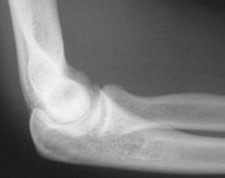

If there are no fractures on the X-ray, the elbow can be reduced immediately. If there are fractures, then the patient may require surgery and orthopedics should be consulted. Following reduction, the patient should have repeat X-rays to determine if the elbow was successfully reduced.

Normal alignment after the elbow has been reduced1